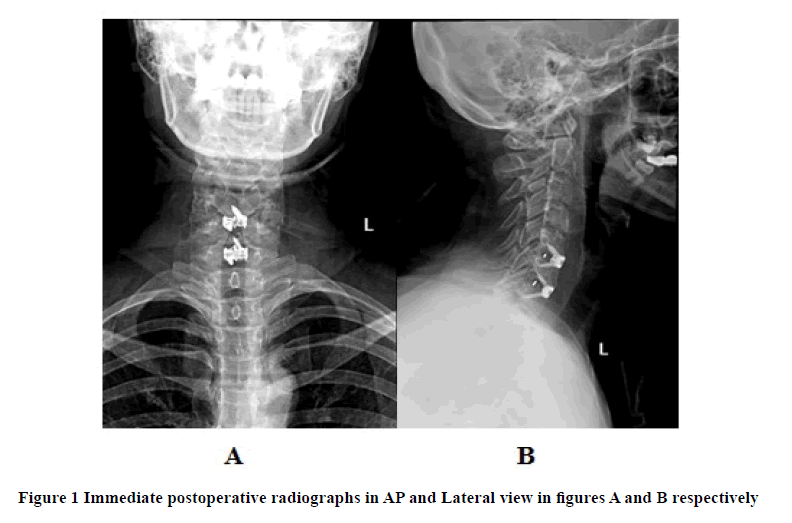

All surgeries were performed under general anesthesia. All the surgeries were performed through a left-sided skin incision in line with a skin crease at the desired level. After identification of the carotid pulsation, blunt dissection was performed to approach the prevertebral fascia. After the prevertebral facia's penetration, the appropriate level was confirmed under the image intensifier, followed by subperiosteal elevation of longus colli muscles and standard discectomy. After preparing the endplates, the suitable size cage is selected using a trail cage, and then the final cage was inserted and secured. Before closure, hemostasis was secured. No drains were used for any patient. The wound was thoroughly irrigated with 0.9% normal saline. Wound closure was performed with vicryl and monocryl. Finally, the antiseptic dressing was applied. Postoperatively all the patients were given rigid cervical collars until six weeks. For all the patients, there were not any intraoperative complications. Postoperative cervical spine X-rays were done (Figure 1).

All the patients were seen in our clinic at three months, and one year after the surgery. Cervical spine X-rays were done at three months (Figure 2) and one year (Figure 3) and calculations were made for disc height to record subsidence.